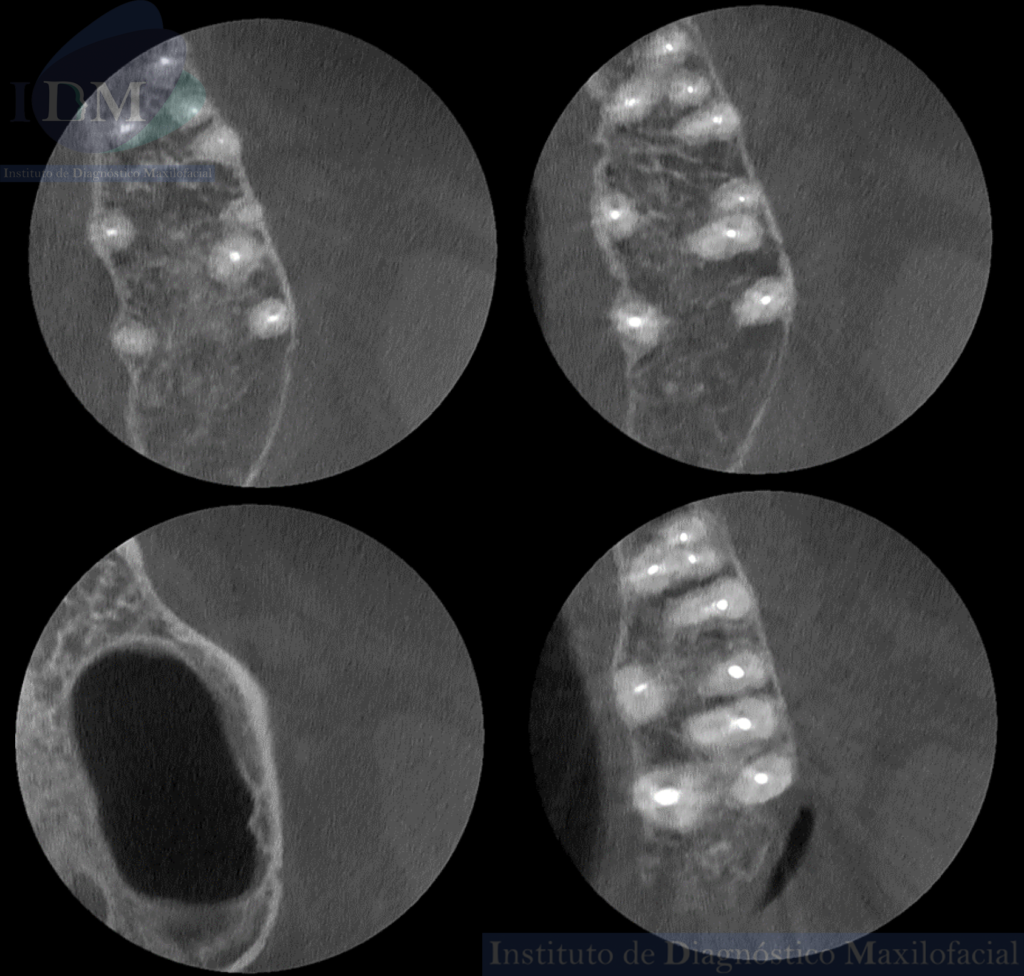

Así mismo en la tomografía volumétrica de haz cónico localizada se evidencia como hallazgo imagenológico, la presencia de tres segmentos radiculares con material de obturación de conductos en la pieza 25. Siendo dos raíces vestibulares (mesial y distal) y una raíz palatina.

CORTES AXIALES

CORTES TRANSAXIALES

- Premolar con tres segmentos radiculares.